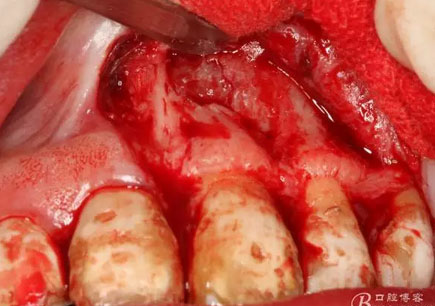

圖12.暴露出的完整囊壁,真夠大!

圖13.完整的從骨壁上剝離囊壁